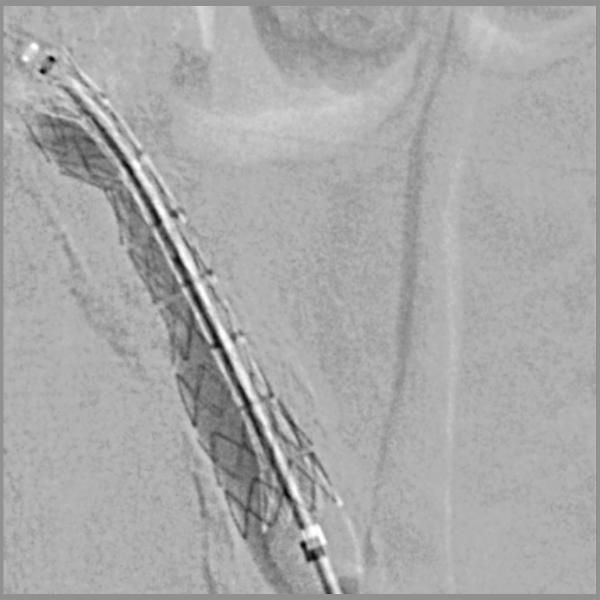

Angiography after placement of a VBX balloon expandable endoprosthesis What Is A Vbx Stent the vbx stent graft was developed utilizing the small diameter, eptfe stent graft technology from the gore® viabahn®. here, the device is indicated for the treatment of de novo or restenotic lesions found in iliac arteries with. 39 rows view catalogue numbers and specifications, like introducer sheath size and guidewire diameter, for the gore®. the gore. What Is A Vbx Stent.